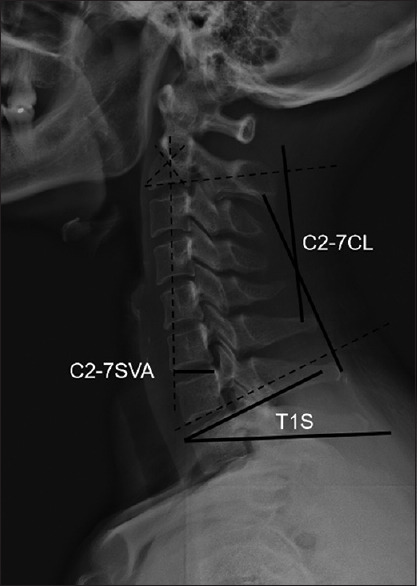

Materials and methods: One hundred thirty-four patients diagnosed with multilevel CSM and a normal matching of T1S-CL were enrolled from the medical records spanning 2015-2020. The anterior group comprised 69 patients, and the posterior group included 65 patients. This study retrospectively analyzed perioperative parameters, including clinical parameters of the Japanese Orthopedic Association (JOA) score, Visual Analog Scale (VAS), neck disability index (NDI), and radiologic parameters T1S, CL, C2-7 sagittal vertical axis (SVA), and T1S-CL.

Results: Prior to surgery, there were no significant differences in factors between two groups (P > 0.05). Postoperatively, while the JOA scores were similar between groups (P > 0.05), the anterior group showed significantly lower in NDI, VAS, perioperative parameters, and incidences of complications (P < 0.001). Significant changes were observed in each group for T1S, CL, C2-7 SVA and T1S-CL (P < 0.001). Preoperatively, in the anterior group, significant correlations were identified between T1S-CL and T1S, CL, and C2-7 SVA (P < 0.05). In the posterior group, significant correlations were observed between T1S-CL and T1S, CL, and C2-7 SVA (P < 0.05). Following surgery, in the anterior group, the correlations persisted between T1S-CL and T1S, CL, and C2-7 SVA (P < 0.05). In the posterior group, the correlations between T1S-CL and T1S, and CL were not significant (P > 0.05). The comparative analysis of parameter changes between anterior and posterior groups revealed no significant difference in the changes of T1S and C2-7 SVA (P > 0.05), whereas significant differences were observed in the changes of C2-7 lordosis and T1S-CL (P < 0.001).